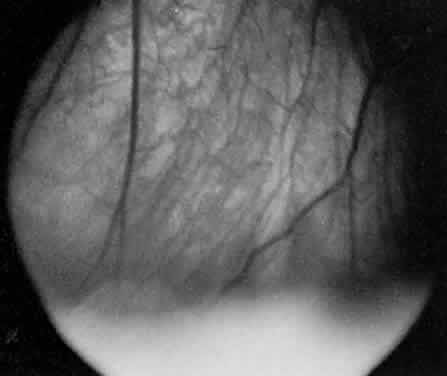

disorder. EPIDEMIOLOGY About 4% to 15% patients referred for uveitis have pars planitis.10–17 Pars planitis usually affects children and young adults.18 It seldom develops before age 5 or after age 30. Most cases develop in the teens and early twenties. In most cases pars planitis enters remission before age 40. Some reports10,18 show no racial predilection, but others11,13,16 show that whites are affected more frequently than blacks. There is no predilection toward either sex.10,18 Pars planitis is bilateral about 71% to 75% of the time.4,13,19 Familial cases of pars planitis and intermediate uveitis have been reported.20–24 SYMPTOMS The onset of symptoms is very gradual in pars planitis. The most common symptoms of pars planitis are blurred vision and floaters. Symptoms may be present for months to years before the patient seeks medical attention. At times, patients with pars planitis are asymptomatic, and the diagnosis is made on a routine ophthalmic examination. Patients with pars planitis rarely report redness, pain, or photophobia. SIGNS Externally, the eyes of patients with pars planitis appear uninflamed. The conjunctiva and sclera are usually white without injection. The cornea is usually clear and appears uninvolved. In long-standing cases, band keratopathy may develop, most frequently in patients who developed pars planitis in childhood or their early teens.11,13 In some cases of pars planitis, small keratic precipitates and fibrin may be present on the corneal endothelium. Large keratic precipitates are not characteristic of pars planitis. The anterior chamber may be clear or show only mild cells and flare. The amount of inflammation in the anterior chamber is typically mild, rarely exceeding grade 2+ .25 The iris may be uninvolved or show only one or two localized posterior synechiae. Extensive iris synechiae, seclusion of pupil, and iris nodules are not typically seen in pars planitis. The lens may be clear or may appear cataractous. In pars planitis, posterior subcapsular cataract is most frequently seen, and it may be the result of ocular inflammation or the chronic use of corticosteroids. In pars planitis, the inflammatory signs are greatest in the vitreous cavity. The vitreous gel is syneretic and shows varying amount of fibrin, cells, and strands. The hallmark of pars planitis is the presence of exudates in the inferior vitreous base (Fig. 1). In early stages these exudates may appear as discontinuous yellow-white clumps (fluffballs or snowballs). However, as the disease progresses, these exudates may increase in number and size until they coalesce to form a fluffy white exudate over the inferior peripheral retina and pars plana. Later, the exudate organizes into a smooth white fibrous-appearing band. This membrane has been termed a snowbank because of its resemblance to white fluffy snow. The term pars planitis is reserved for intermediate uveitis in which snowbank is present. The amount of vitreous inflammation is usually symmetric in both eyes. However, in some cases, a prominent snowbank may be present in one eye but only a few fluff balls in the other. Scleral indentation is often required to visualize the snowbank (Fig. 2).7,26